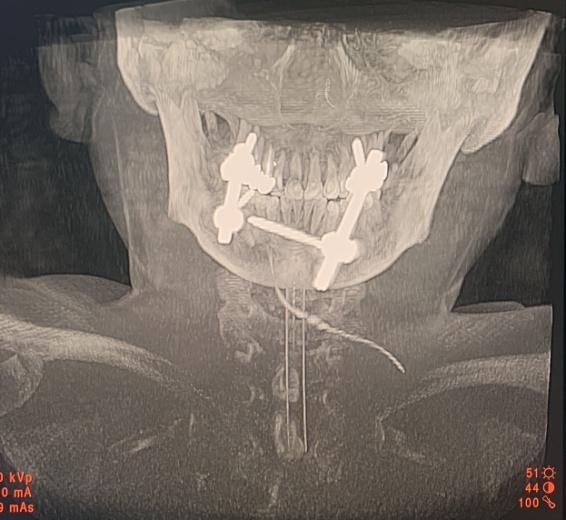

术中取骨融合术后照片

术后颈椎三维CT成像:内固定物位置良好,寰枢椎脱位复位满意